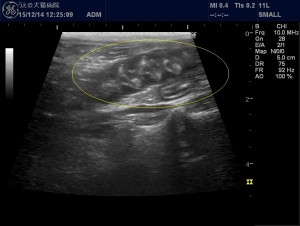

こちらは腸の超音波画像になります。

小腸を黄色丸で囲ってあります。これは正常な部分の腸です。